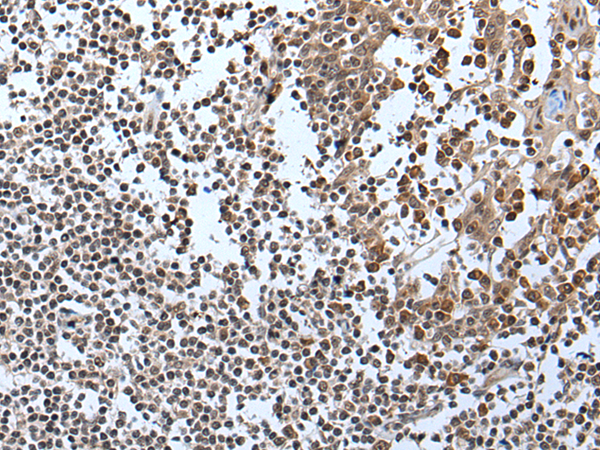

分类: 科研抗体货号: P12899别名: IGI; IGVPB; VPREB; CD179a应用: IHC反应种属: Human